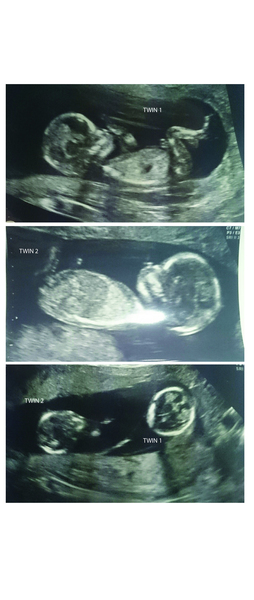

GuybrushThreepwoodMP · 12/05/2015 11:11

Scan pics. Had to take a photo of the prints because hospital isn't high-tech enough to give me electronic versions! Twin 1 is slightly more photogenic but they both looked happy and chilled out. All good.

Two babies though! Fucking hell. Still can't quite get my head around it. Three children. Didn't plan that!

guy those pictures are fab. 2 babies! Are you slowly getting used to the idea of 2?